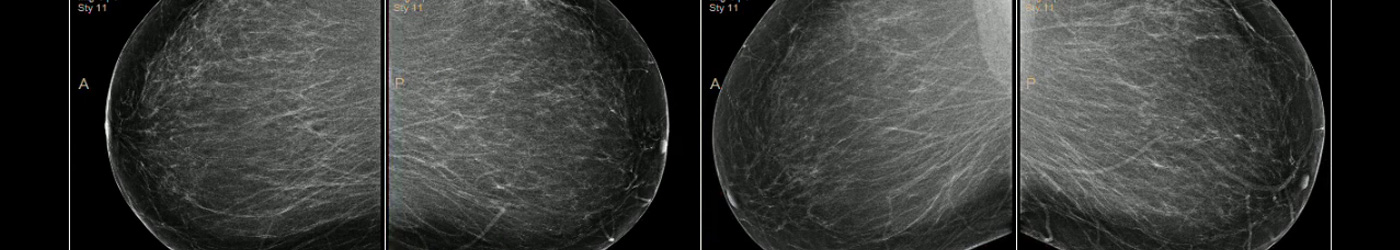

Desde 1996 somos el área de referencia para el programa de cribado poblacional de cáncer de mama. En 2004 incorporamos dos unidades de mamografía digital de campo completo con detectores de selenio, consiguiendo trabajar sin placas desde junio de 2004 y disponiendo de todos los estudios tanto de la mamografía de cribado como asistencial en el archivo digital (PACS) . Durante el año 2005 incorporamos el nuevo sistema de detección digital por ordenador (CAD).